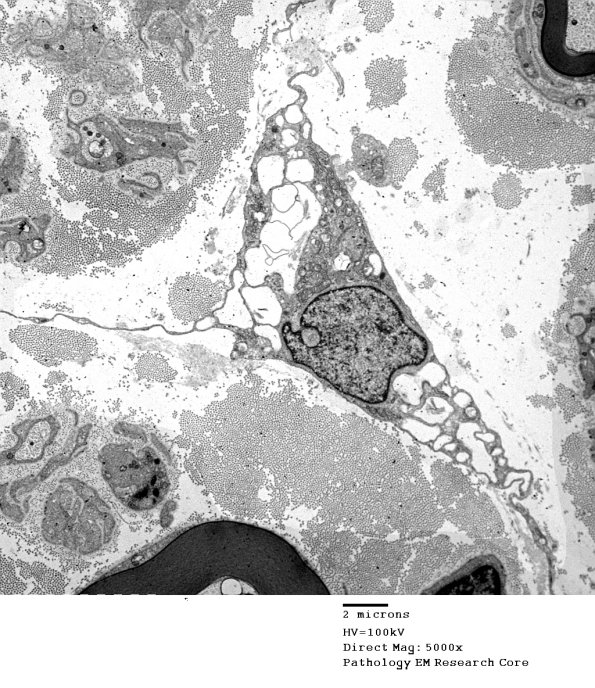

Additional examples of vacuolated fibroblasts. (electron micrographs)